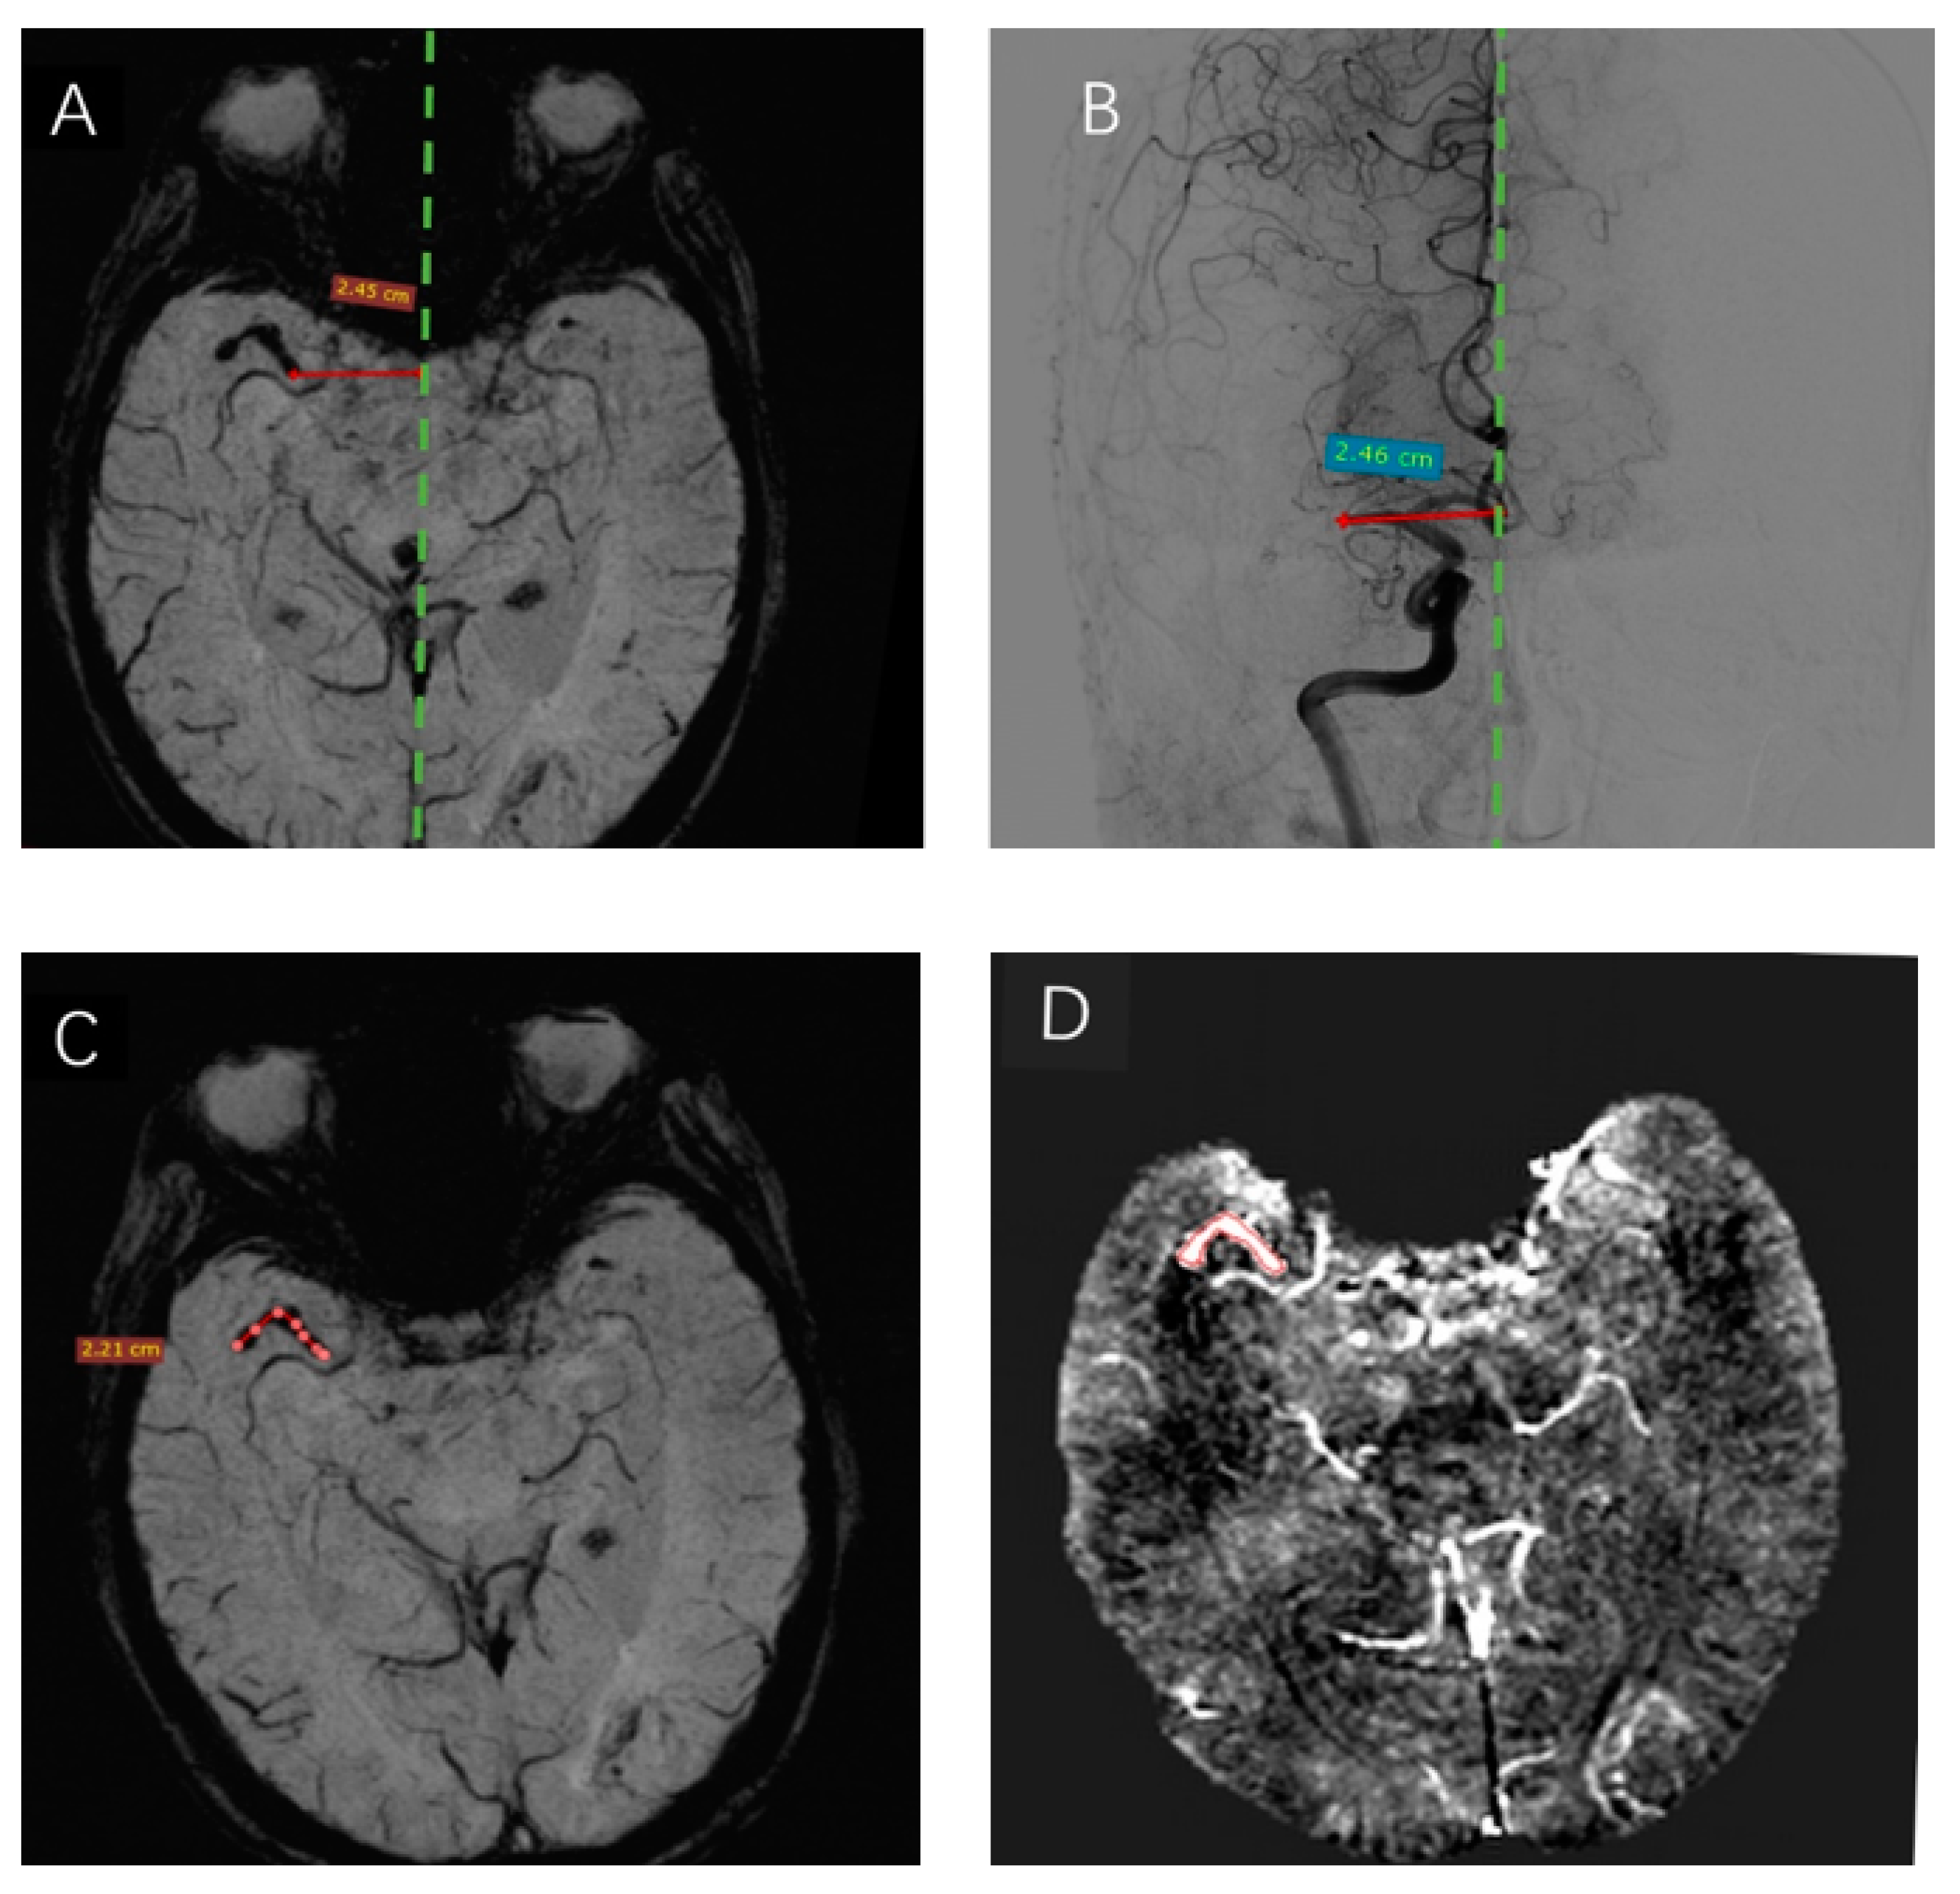

Figure 3.

SWI and DSA demonstration of the thrombus. A thrombus was visible in the right MCA on SWI (mIP). The distance from the proximal end of the thrombus to the midline on SWI (A) was highly similar to that measured on DSA (B). The length of the thrombus measured on SWI was 2.21 cm (C). (D) The ROI is drawn in axial view at the central slice of the thrombus, with a mean susceptibility value of 212.1 ppb (In red contour).

2.5. Measurement of the Length of Thrombi and Analysis

The location of the SVS was used to denote the position of the thrombus in relation to the midline. The midline was defined as a line connecting the occipital part of the superior sagittal sinus with the point midway between the A2 segments of the anterior cerebral arteries, as observed on axial images. The maximum thrombus length was measured on SWI using a previously published method [17]. The diagnostic series of DSA images were analyzed for the presence and location of the occluding thrombus according to the criteria used for SWI. The detailed measurements are shown in Figure 3A–C. The measurements were completed by two radiologists unaware of SVS on SWI and the location of the occlusion on SWI and DSA.

3. Results

A total of 15 patients consisting of 40% males, mean age ot 73.47 ± 10.7 (range 59–88) years, were included in the final analysis. The clinical characteristics of these patients are summarized in Table 1. Among these patients, 10 had an occlusion of the M1, 3 had M2, and 2 had both the M1 and M2 segments. All patients underwent thrombectomy with successful retrieval of their thrombi. The gold standard DSA showed vessel occlusion in all patients. The average distance of the proximal end of the thrombi to the midline was 24.67 ± 8.43 mm and 24.62 ± 8.44 mm as measured by SWI and DSA, respectively (Figure 3A,B), there was no difference in the detection of thrombus initiation between the two groups. Also, the SVS of SWI can directly measure the curve of thrombi length of 2.21 cm (Figure 3C), and the mean thrombus length of 15 cases was 16.57 ± 4.6 mm. The susceptibility of each region of interest (ROI) of the thrombus was measured manually and shown directly by the SPIN software (Figure 3D). The mean susceptibility values of RBC-dominant thrombi and fibrin-dominant thrombi were 209.88 ± 11.32 ppb and 155.70 ± 28.20 ppb, respectively. The mean thrombus susceptibility of RBC-dominant thrombi was significantly higher than that of fibrin-dominant thrombi (p = 0.037).